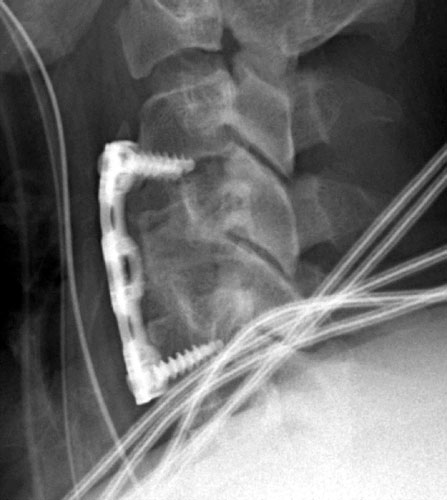

Immediate post-operative lateral radiograph demonstrating cortical fixation screws traversing the C3-4 disc space.